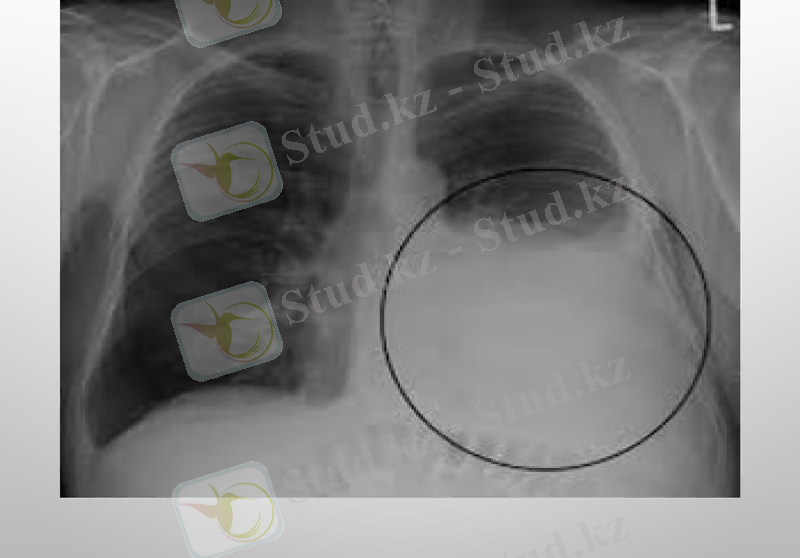

Плеврит - плевра қуысында сұйықтықтың жиналуы. Плевра - көкіректің ішкі бетін астарлап жататын сірі қабық.

Плевритті шартты түрде құрғақ (фибринозды) және іріңдік (экссудативті) деп бөледі. Құрғақ Плеврит кезінде сірлі қабық ісініп, қалыңдайды да қабыну процесі басталады. Ал іріңдік Плевритте плевра қуысы қан, ірің аралас сұйықтыққа толып кетеді. Адамда туберкулезді Плеврит жиі кездеседі. Плевриттің бұл түрі өкпеде немесе лимфа түйіндерінде басталып, кейін өкпені түгел қабындырады. Науқастың дене қызуы көтеріліп, құрғақ жөтел пайда болады.

Плевриттің диагностикасында рентгенография рентгеноскопии кеуде жасушаларының, плевральді қуыста УЗИ, плевральді пункции, диагностикалық торакоскопия жасалынады.

Туберкулезді плеврит